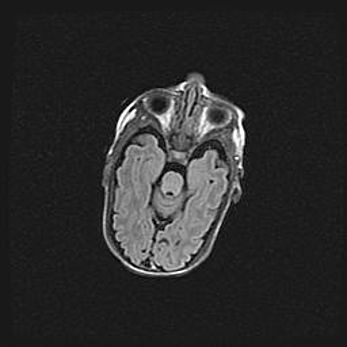

Сообщающаяся гидроцефалия. Кистозная энцефаломаляция головного мозга.

Возраст: 3 месяца 4 дня

Вес: 3100 г

Пол: женский

Окружность головы: 34 см

Срок гестации: 31 неделя

Кистозная энцефаломаляция головного мозга - одна из форм поражения головного мозга в детском возрасте. Характеризуется возникновением множественных и распространённых кист в коре, белом веществе и подкорковых образованиях головного мозга у плодов, новорождённых и детей раннего возраста. Развитие кистозной энцефаломаляции связано с внутриутробной асфиксией и гипотонией, родовой травмой, тромбозом синусов, пороками развития сосудов, инфекциями, сепсисом и другими причинами. Наиболее значимые инфекционные агенты: вирусы простого герпеса, цитомегалии, краснухи, токсоплазмы, энтеробактерии, золотистый стафилококк и другие.